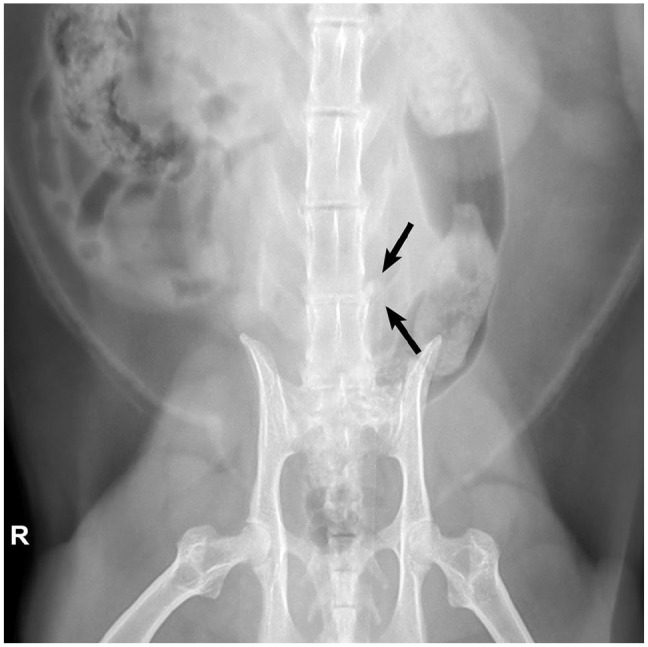

Case summary: A 9-year-old male castrated domestic shorthair cat was presented with a 2-week history of acute, progressive left pelvic limb lameness. Gait evaluation revealed a grade 3/5 left pelvic limb lameness with no apparent orthopedic cause for the lameness based on orthopedic examination or radiographs. The neurological examination was otherwise normal. MRI revealed a left-sided L6-7 far lateral intervertebral disc extrusion with possible secondary neuritis of the L6 spinal nerve. A left-sided L6-7 foraminotomy was performed to remove the extruded disc material and provide additional space for the significantly enlarged nerve root. An L6-7 fenestration was also performed. The patient made an excellent recovery with near-complete resolution of lameness at 26 days postoperatively.